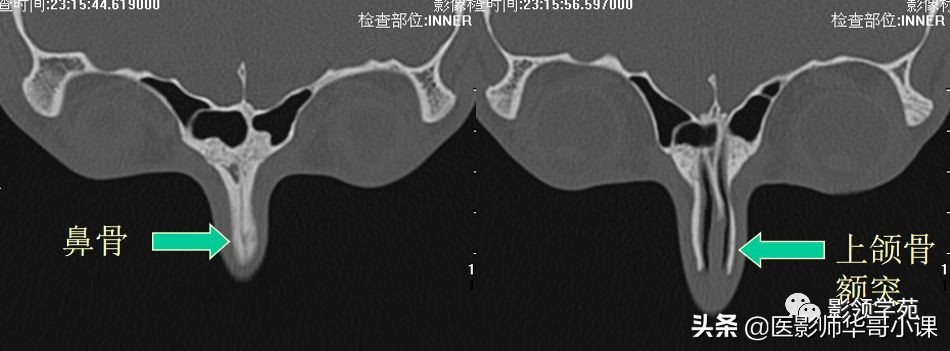

鼻骨解剖

- 位于两上颌骨额突之间

- 构成鼻腔上部

- 长方形

- 上端窄、厚,下端宽、薄

- 两面、四缘

鼻骨邻近骨性结构

- 上颌骨额突

鼻骨正常侧位

鼻骨横断面HRCT

鼻骨冠状面HRCT